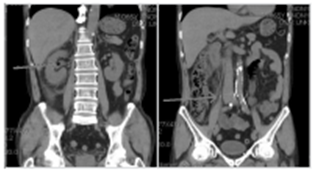

예시 1) 58세 남성, Rt. flank pain 및 UA상 hematuria로 응급실 내원

사진설명: nonenhanced CT에서 Rt. hydronephrosis및 proximal ureter stone이 보임.

환자는 진통제 투여 후 통증이 호전되어 외래에서 추적관찰을 하기로 함.

<figure-inline>전공의핸드북 그림6.png</figure-inline>

사진설명: 2주 후 nonenhanced CT에서 Rt. hydronephrosis 소실 소견이 보이지만 Rt. mid-ureter에 stone이 지속되고 있음.

<figure-inline>전공의핸드북 그림7.png</figure-inline>

진단 및 치료적 ureteroscopy을 시행하기로 함.

좌측 사진은 상기 환자의 Rt. ureteral orifice에 urothelial neoplasm이 있는 사진이고 우측 사진은 이를 제거하고 ureteroscopy를 시행하였을 때 보이는 ureter내 urothelial neoplasm의 모습이다.